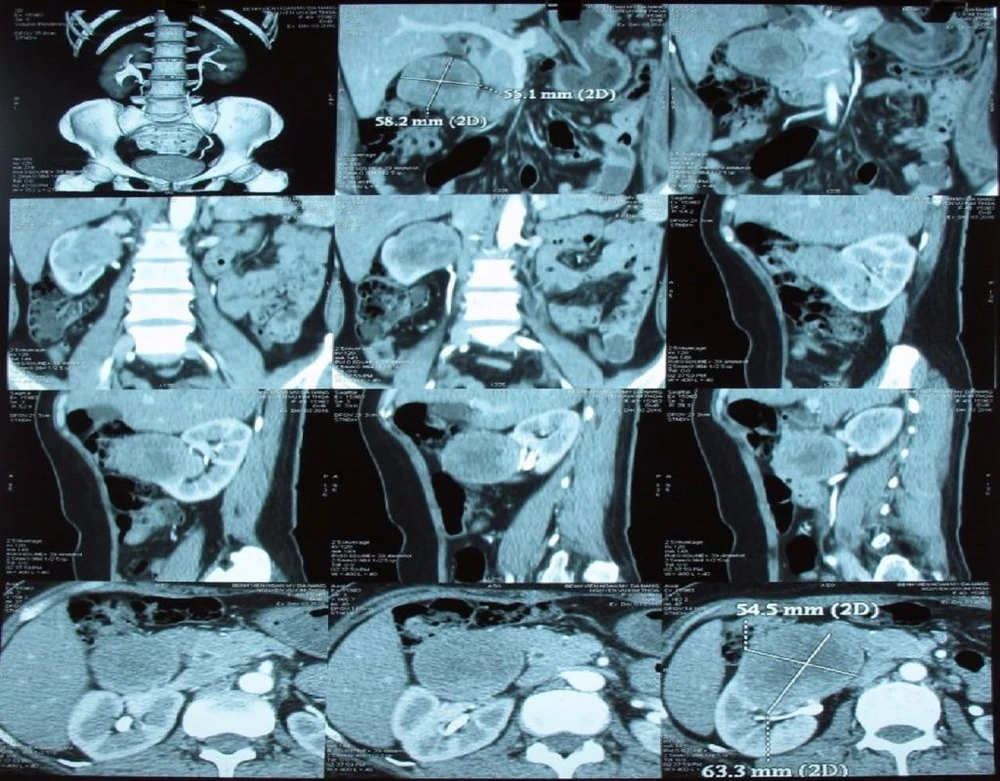

Ngày 20-12, BV ĐH Y Dược TP.HCM cho biết BV vừa điều trị thành công cho bệnh nhân NTT (24 tuổi, ngụ TP.HCM) bị bướu thận. Trước đó, bệnh nhân đến khám với triệu chứng tức nhẹ ở vùng hông lưng, không có rối loạn tiêu tiểu. Tuy nhiên, sau siêu âm bụng và chụp CT - scan, bác sĩ phát hiện người bệnh có khối bướu thận trái với kích thước khá lớn khoảng 5 cm.

Bệnh nhân T. được chỉ định phẫu thuật nội soi cắt bướu bảo tồn thận để điều trị. Hiện chị T. đã phục hồi và sức khỏe ổn định sau mổ nhờ phẫu thuật nội soi.

Đa số ung thư thận thường gặp ở độ tuổi 50-70, tuy nhiên trường hợp người bệnh ở trên là một minh chứng ung thư thận có thể xảy ra ở độ tuổi rất trẻ. Ung thư thận ở giai đoạn sớm khi kích thước bướu còn dưới 7 cm, thường không có triệu chứng điển hình. Ở giai đoạn muộn, khoảng 30% người bệnh có các triệu chứng đau bụng, tiểu máu, thăm khám thấy có khối u bụng.

Ung thư thận ở giai đoạn sớm khi kích thước bướu còn dưới 7 cm, thường không có triệu chứng điển hình. ẢNH:HP